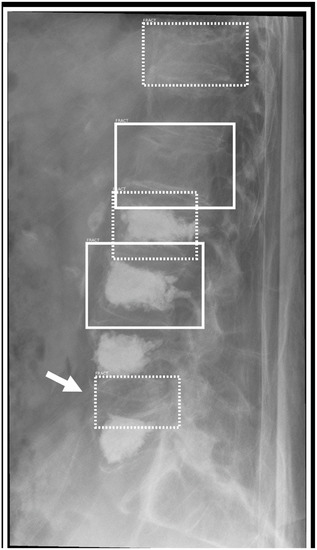

3.3. Sensitivity and Specificity by Anatomical Region

| Spine | 92.39% | 98.43% | 89.13% | 62.20% | 94.57% | 100.00% |